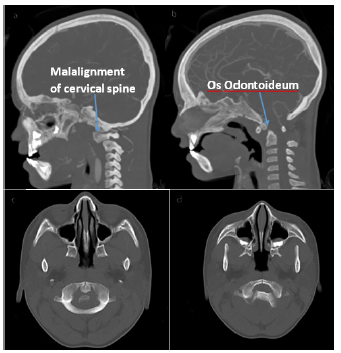

Before initiation of steroids the patient’s neurologic exam started to improve and he and was able to sit up in bed independently. Within 48 hours he was able to ambulate and was near baseline energy level. Due to his unusual clinical course and concern that imaging was inconsistent with transverse myelitis, specifically the hemorrhagic component, further investigation was conducted. A CT head and neck angiogram was performed to look for a vascular injury or anomaly that may have led to the hemorrhage. Results demonstrated suspected unstable cranio-cervical junction with os odontoideum, malalignment, and cervical stenosis (Figure 2). When compared to the recent MRI, the cord signal abnormality may have represented traumatic injury as opposed to inflammation.

Neurosurgery was consulted and believed the findings were from recurrent trauma to the cervico-medullary segment due atlantoaxial subluxation. The patient was placed in a hard c-collar for stabilization and taken to the operating room for C1-C2 spinal fusion. He was discharged home in stable condition.